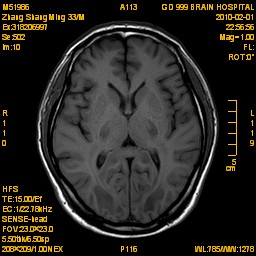

案例1 患者,男,33岁, 海洛因脑病的头颅MR。表现为双侧大脑后部皮层下白质、双侧内囊后肢、枕叶白质、胼胝体压部、中脑、桥脑、双侧小脑半球齿状核质及双侧桥臂多发对称性片状及斑片状长T1长T2异常信号影,FLAIR序列呈高信号,其中双侧内囊后肢表现为特异的“八字征”,双侧小脑半球齿状

核质表现为对称的“蝶翼征”,脑干病变呈“蟹钳征”及“中空征”。增强后双侧半卵圆中心、双侧枕叶白质及双侧小脑半球病变内或边缘中度强化影。给予患者抗炎、脱水、疏通血管及营养神经等药物治疗,一个月后痊愈出院。